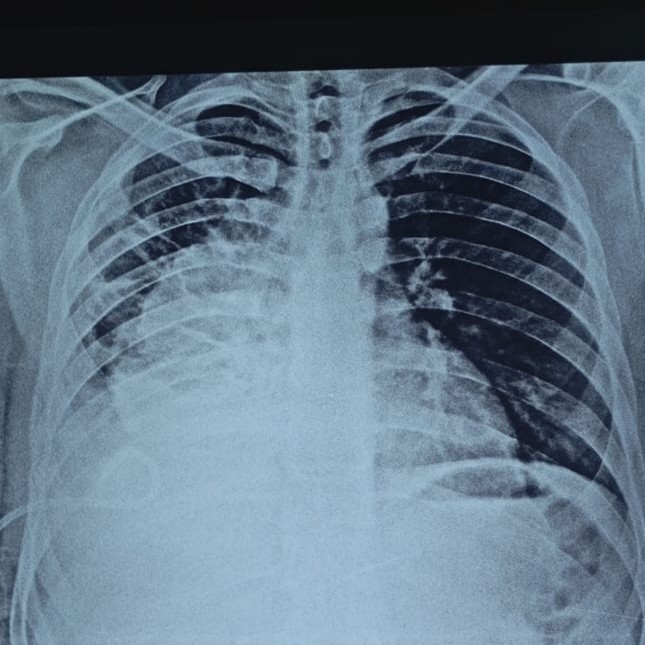

pleural effusion treatment

Pleural effusion is collection of fluid around lung. Often need removal by needle insertion. Meet chest specialist for advise